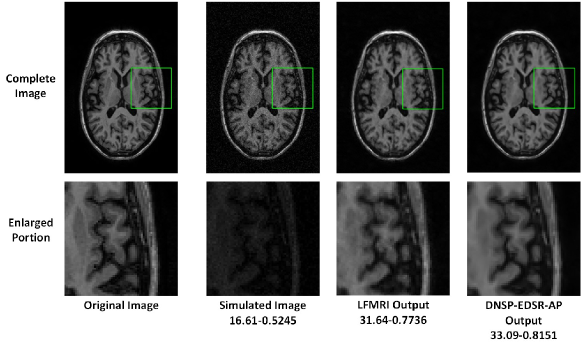

Figure 12: Comparisons of top 4 methods for an image in ADNI dataset for scale factor of 2. A small portion of the images (marked by green box) in the first row is zoomed in and shown in second row. The numerical figures constitute the respective PSNR-SSIM values.

Table II shows PSNR and SSIM values for all competing methods. Note that we used two different base networks for DNSP: 1) DNSP-SRCNN-AP - the base network is SRCNN and 2) DNSP-EDSR-AP - the base network is EDSR. Three trends emerge from the results: 1) DNSP-EDSR-AP outperforms the competition, 2) DNSP-SRCNN-AP does better than all the methods except EDSR, and 3) overall, deep SR methods, i.e. SRCNN, EDSR, DCSRN and DNSP perform better than other alternatives. To confirm this statistically, we performed a 2-way Analysis of Variance (ANOVA) on PSNR values for all the methods across the two datasets which is illustrated in Fig. 10. It may be inferred from Fig. 10 that deep learning methods are statistically well separated from the traditional methods and further DNSP-EDSR-AP is well separated from all the competing methods indicating the effectiveness of using prior information. Figures 11 and 12 illustrate the results of the top 4 methods w.r.t. PSNR on a sample image from BW and ADNI databases respectively for a down-sampling factor of 2 while Figures 13 and 14 show results for a down-sampling factor of 4. DNSP-EDSR-AP particularly excels in recovering fine image detail (enlarged with zoom-in boxes), thanks to data-adaptive sharpness.